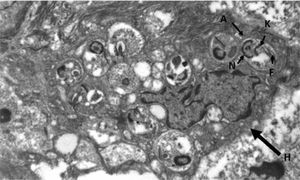

Dysphonia is the most common symptom in laryngeal leishmaniasis and indirect laryngoscopy usually shows localised lesions with an irregular and even ulcerated surface which raise a differential diagnosis with cancer.5 Clinical suspicion is rare when it is not associated with VL or CL, as in our case, and so it is essential to perform a biopsy to make a differential diagnosis with cancer or other chronic granulomatous diseases such as Paracoccidioides, Blastomyces, Actinomyces and histoplasma (in endemic areas).8 Histologically, it is characterised by non-necrotising granulomatous inflammation with the presence of abundant amastigotes within the histiocytes, which we identify as small ovoid bodies whose nucleus and kinetoplast stain with Giemsa and CD1a.9 Electron microscopy confirmed the presence of amastigotes (Fig. 3), but for the definitive diagnosis, confirmation and typing of the species is required by PCR and subsequent sequencing of the parasite's DNA10 which, as in our case, can be performed from samples previously paraffin-embedded.